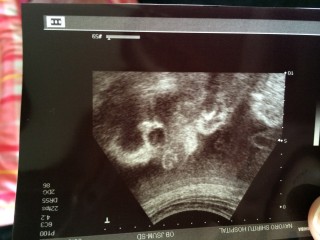

前から男の子だといわれていましたが確定しました。シンボルをはっきり写してくださいました!笑 それがこの写真です。ごめんよ息子。笑 足が長くてスマートな子との事。逆子でした。口はパクパク、目もキョロキョロさせて愛おしかったです。早く会いたいな。